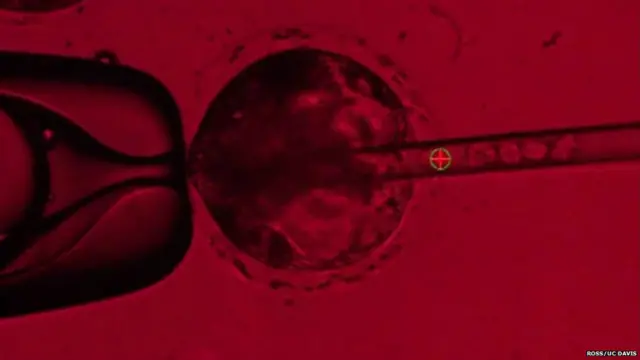

这样的胚胎合成技术牵涉两个阶段。首先,研究人员须利用称为CRISPR的基因剪辑技术,去除新受精猪胚胎中让胰脏生成的基因,以形成基因“壁龛”。

然后,科学家会把诱导性多功能干细胞(iPS)注射到胚胎里面。这些iPS细胞是从成年人细胞中分离出来,再“回拨”成可以发育成任何组织的干细胞。

图像来源,Pablo Ross at UC Davis